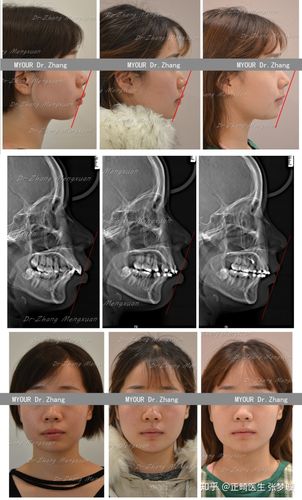

龅牙矫正脸型改变有多大?

牙齿扩弓前后脸型变化